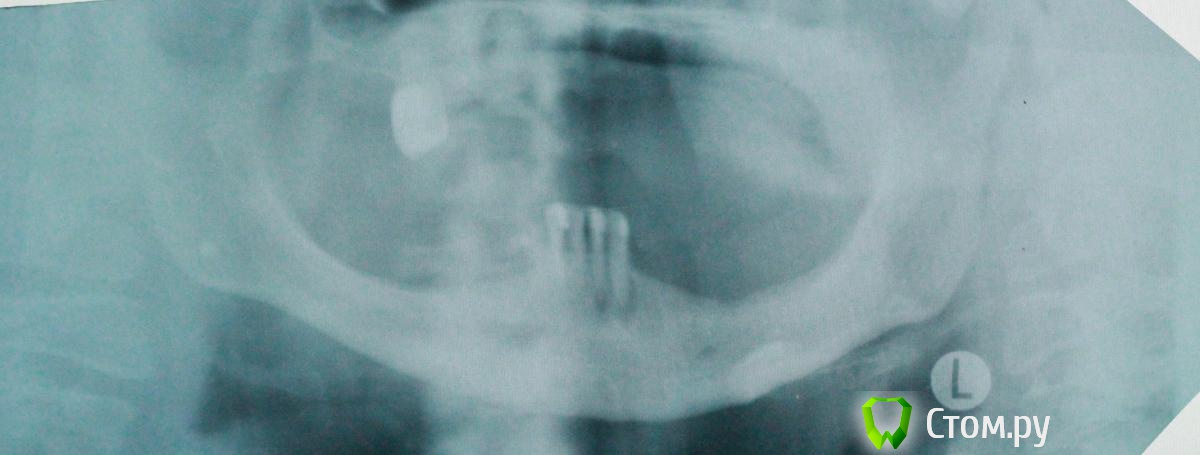

Фарид Расулыч Опубликовано 19 июня, 2014 Поделиться Опубликовано 19 июня, 2014 Добрый день. Обратилась пациентка 52 года. Настаивает на имплантации, изначально хотели тотальную имплантацию нижней челюсти, но, после взгляда на ОПТГ этот вариант отпал. Высота кости до нижнечелюстного нерва (~ 0,5 см, ширина альвеолярного отростка "пальпаторно" 1 см.) На данный момент мне в голову приходит только один вариант: удаление четырех нижних резцов, 2 импланта, один в область 42, второй в область 33. Полный съемный протез на лок абатментах. Кто что думает по этому поводу? или есть альтернативы? п.с. Качество ОПТГ удручающее.... Ссылка на комментарий

Bier Опубликовано 19 июня, 2014 Поделиться Опубликовано 19 июня, 2014 тот случай, где хотелось бы посмотреть на КТ ) 3 Ссылка на комментарий

kriokov Опубликовано 19 июня, 2014 Поделиться Опубликовано 19 июня, 2014 +1 к КТПо орто похоже, что четыре винта под локаторы можно вкрутить в стандартные позиции 2 Ссылка на комментарий